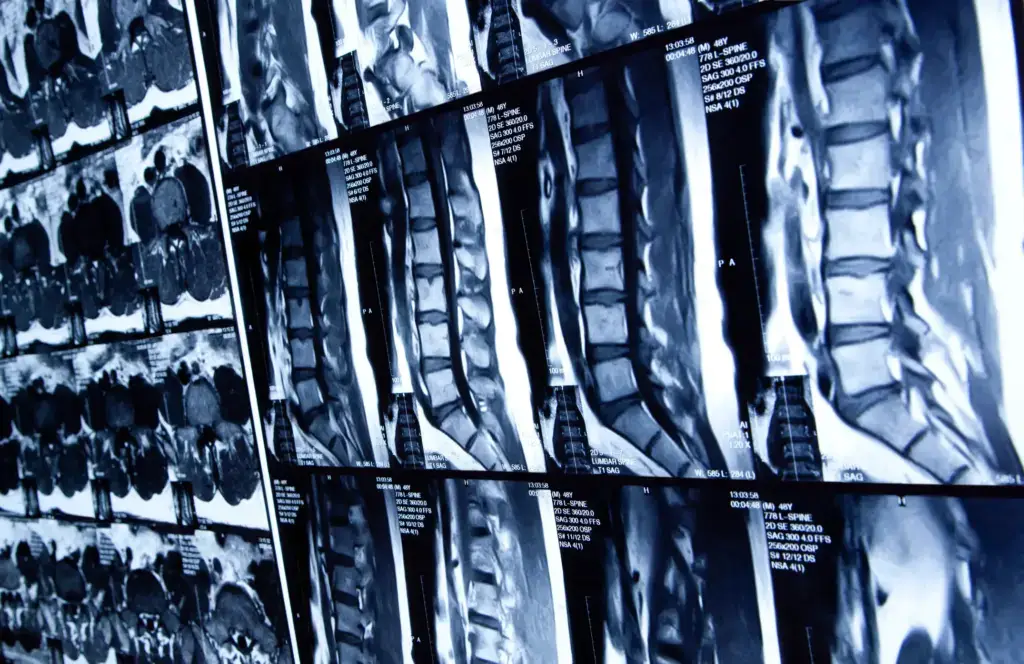

What Happens When the Spinal Cord Is Injured?

When the spinal cord is injured, it can impair the nervous system’s communication pathways. This may lead to partial or complete paralysis depending on which region is mostly affected. The extent of harm will depend on the location and the severity of damage.

Injured victims will need to undergo extensive medical procedures and rehabilitation to improve their quality of life. In the weeks and months that follow, some may notice improvement to a certain degree, but full recovery is not usually possible.

What Is the Classification of Spinal Cord Injuries?

The ASIA Impairment Scale (AIS) grades the extent of spinal cord injuries from A to E. A will represent a complete injury with no motor or sensory function below the injury. Grade B will indicate that there is feeling, but no movement. Grades C and D will show various levels of movement, with D having more strength preserved. Grade E means normal movement and feeling. This scale will allow physicians to understand the injury, determine how rehabilitation will be done, and monitor the recovery over time. As spinal cord injuries are classified based on the severity and the type of neurological impairment, it can be furthered categorized as either complete or incomplete.

What Are the 4 Types of Spinal Cord Injuries?

The four types of spinal cord injuries are determined based on the region of the spine impacted by brute force or by illness. These include: cervical, thoracic, lumbar, and sacral. Let’s take a closer look at each one below.